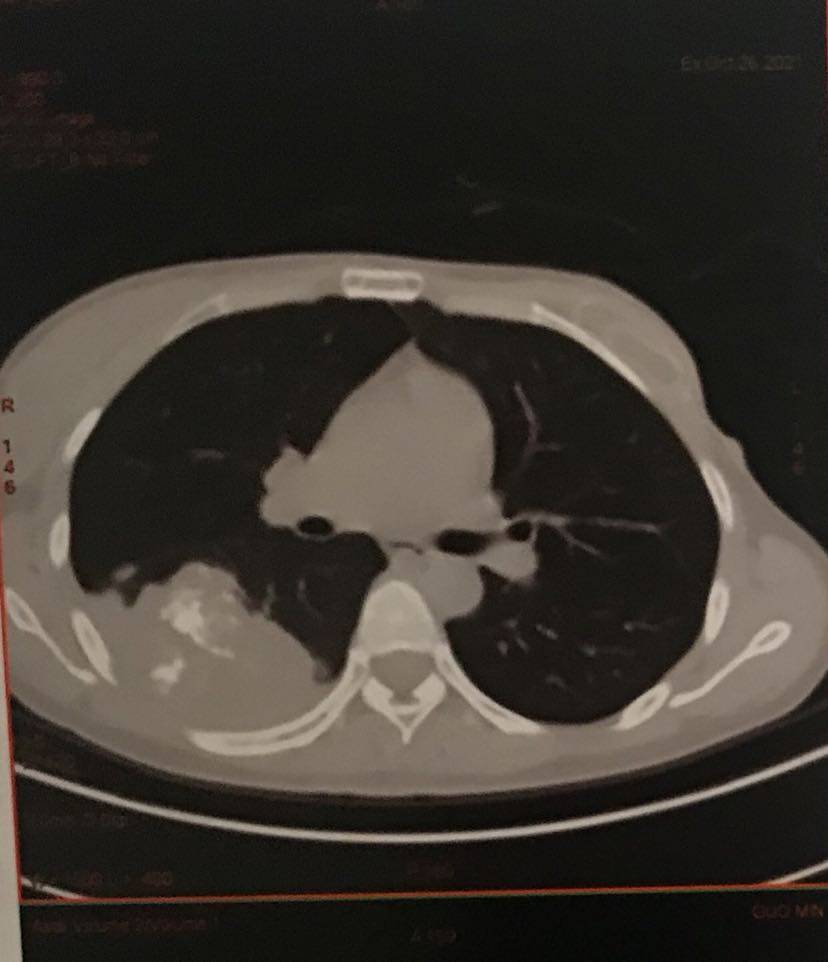

10月26日肿瘤变大了一些